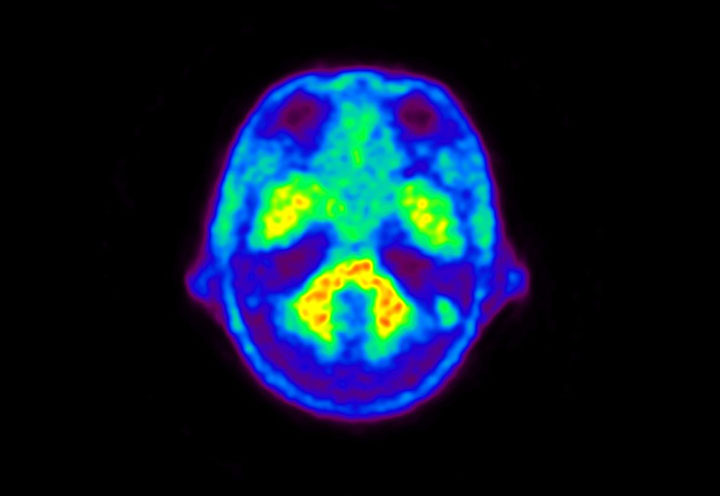

Head / Case5 : Amyloid

Courtesy : Kindai University Hospital

- Imaging protocol

- Injected dose: 4.27 MBq/kg, 18F-Flutemetamol

- Uptake time: 99 minutes

- Scan time: 20 minutes